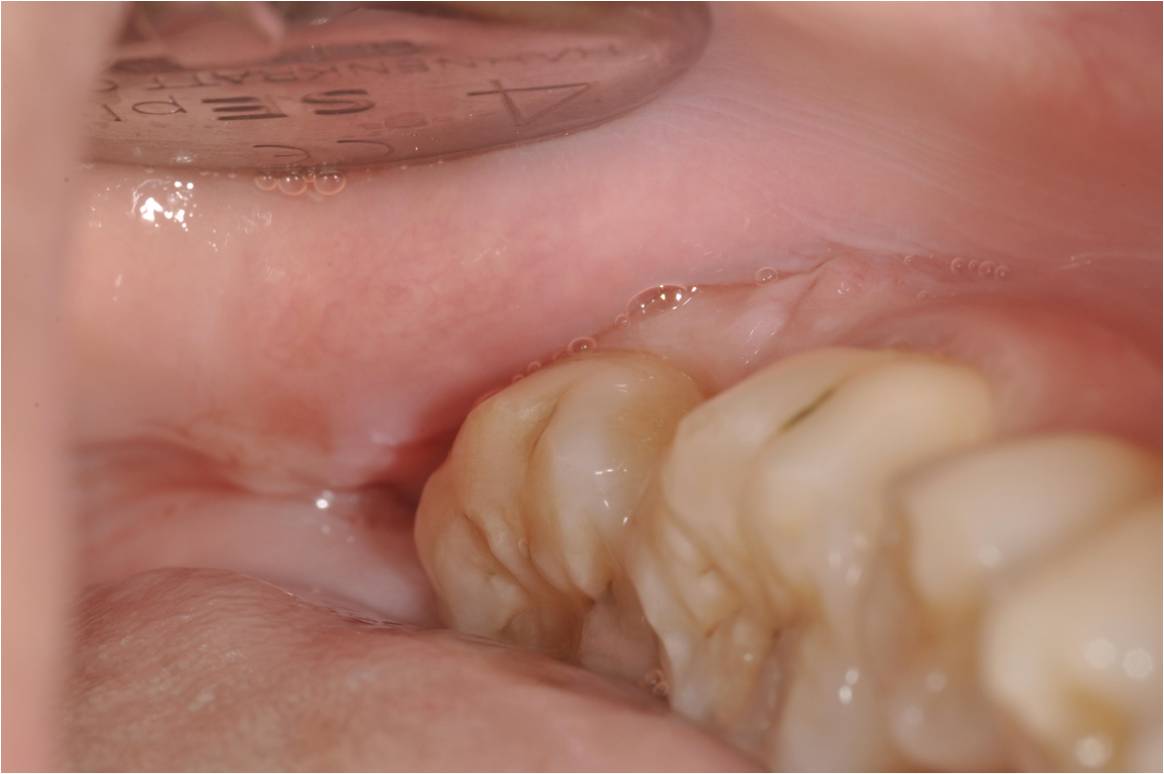

左下阻生齒:拔牙及補膠原

術後1週